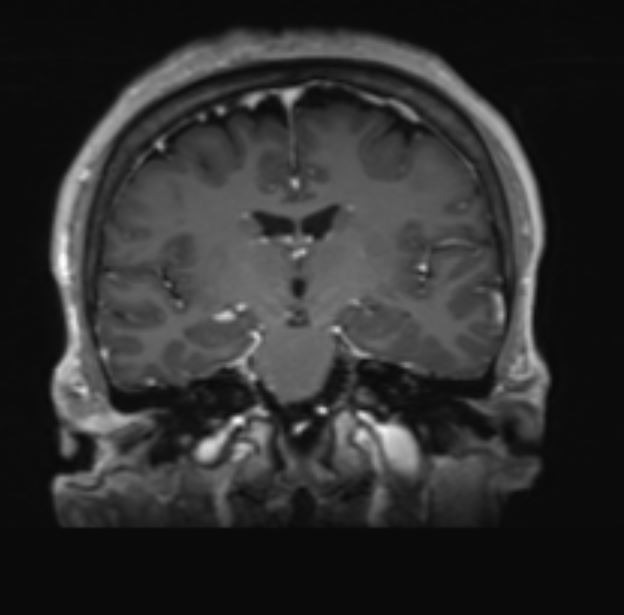

Η μετεγχειρητική μαγνητική τομογραφία ανέδειξε πλήρη εξαίρεση του όγκου (βλ εικόνες).

Το μεγαλύτερο τμήμα του όγκου προσπελάσθηκε μέσω μιας τυπικής οπισθοσιγμοειδικής κρανιοτομίας όμως πρόβλημα αποτελούσε το τμήμα του όγκου το οποίο επεκτείνονταν στην περιοχή του γαγγλίου. Προκειμένω να αφαιρεθεί και αυτό το κομμάτι του όγκου “ανοίξαμε” την κορυφή του λιθοειδούς αφαιρώντας το οστικό έπαρμα ύπερθεν του εσω ακουστικού πόρου, μια απαιτητική και ιδιαιτερη τεχνική. Έτσι καταφέραμε την ολική εξαίρεση της βλάβης και την απαλλαγή της ασθενούς από τα συμπτώματά της.